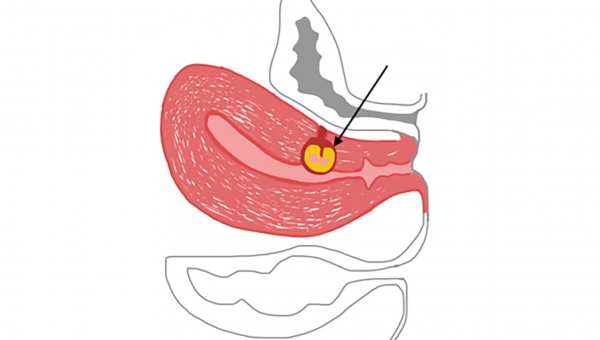

Es considerada una forma novedosa y potencialmente mortal de implantación anormal de un saco gestacional dentro del miometrio y el tejido fibroso de la cicatriz.

Hay quienes también le llaman “istmocele”, “embarazo ectópico en la cicatriz de la cesárea”. Sin embargo, algunos grupos prefieren hacer la diferencia con el embarazo ectópico “verdadero”: tubario, cornual, intersticial y cervical.